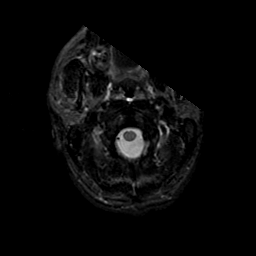

MR Study #23, January 26, 1992 -- Slice #1